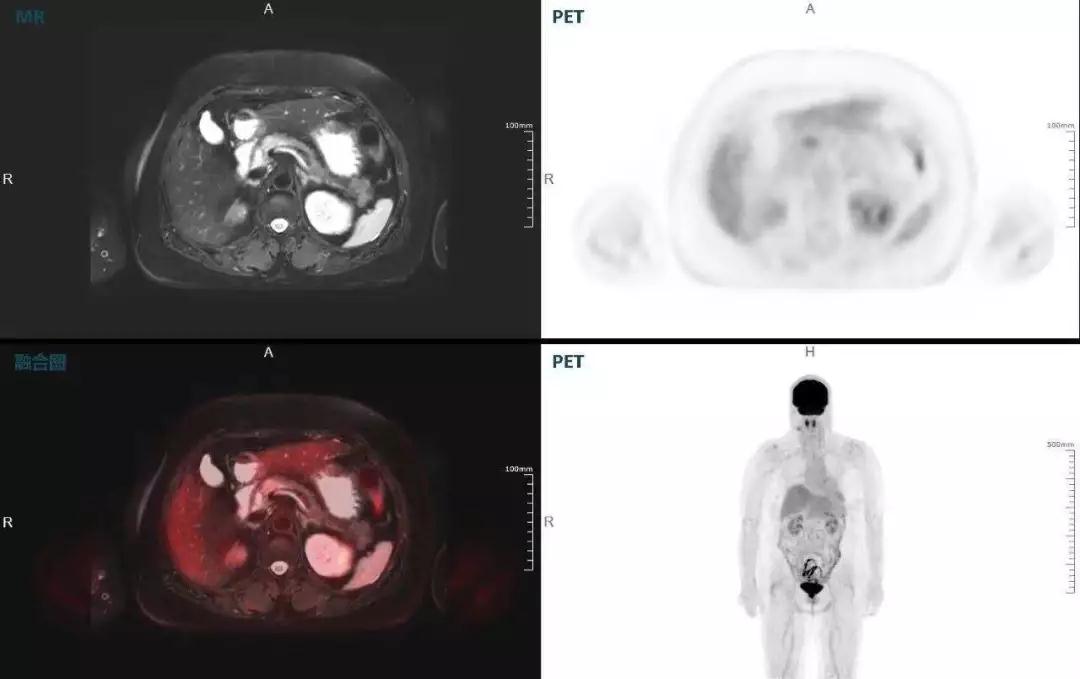

胰腺癌

中山醫(yī)院核醫(yī)學(xué)科在臨床實(shí)踐中發(fā)現(xiàn),基于聯(lián)影“時(shí)空一體”超清TOF PET/MR,不僅解剖信息和代謝信息能夠完美融合呈現(xiàn),同時(shí)精細(xì)展示局部病灶與周圍組織的復(fù)雜關(guān)系,并能全盤檢測(cè)病灶的全身轉(zhuǎn)移,為醫(yī)生臨床診斷提供更豐富信息。

(胰腺腫瘤,MR顯示胰腺體部信號(hào)異常,PET顯示稍高攝取,結(jié)構(gòu)改變和功能異常提示胰腺M(fèi)T可能大。)